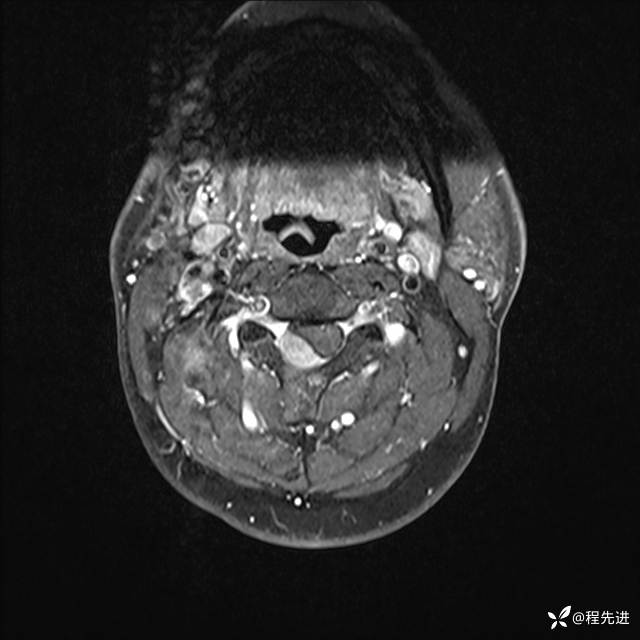

MRI平扫+增强:

T1增强: